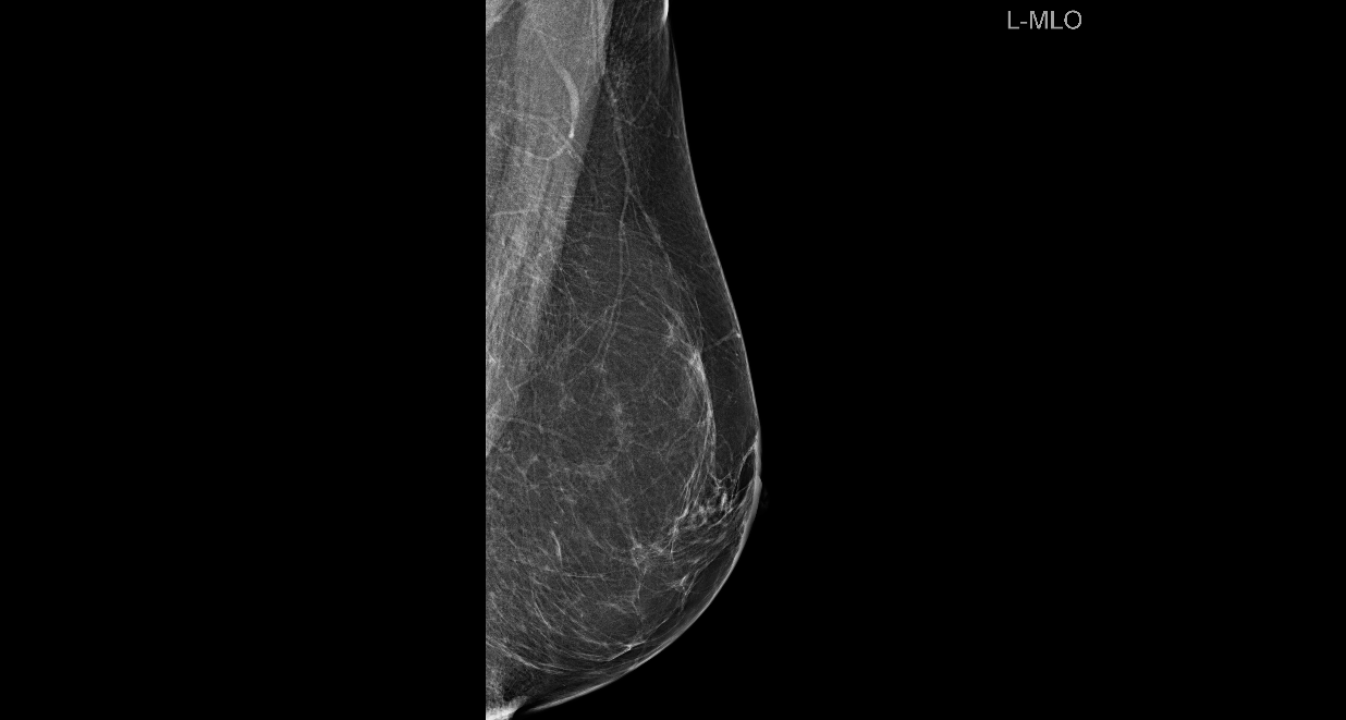

Zakažite preventivni pregled dojke u poliklinici Affidea Vita!

Listopad je mjesec borbe protiv raka dojke, najčešćeg raka od kojeg obolijeva jedna od deset žena u Hrvatskoj.